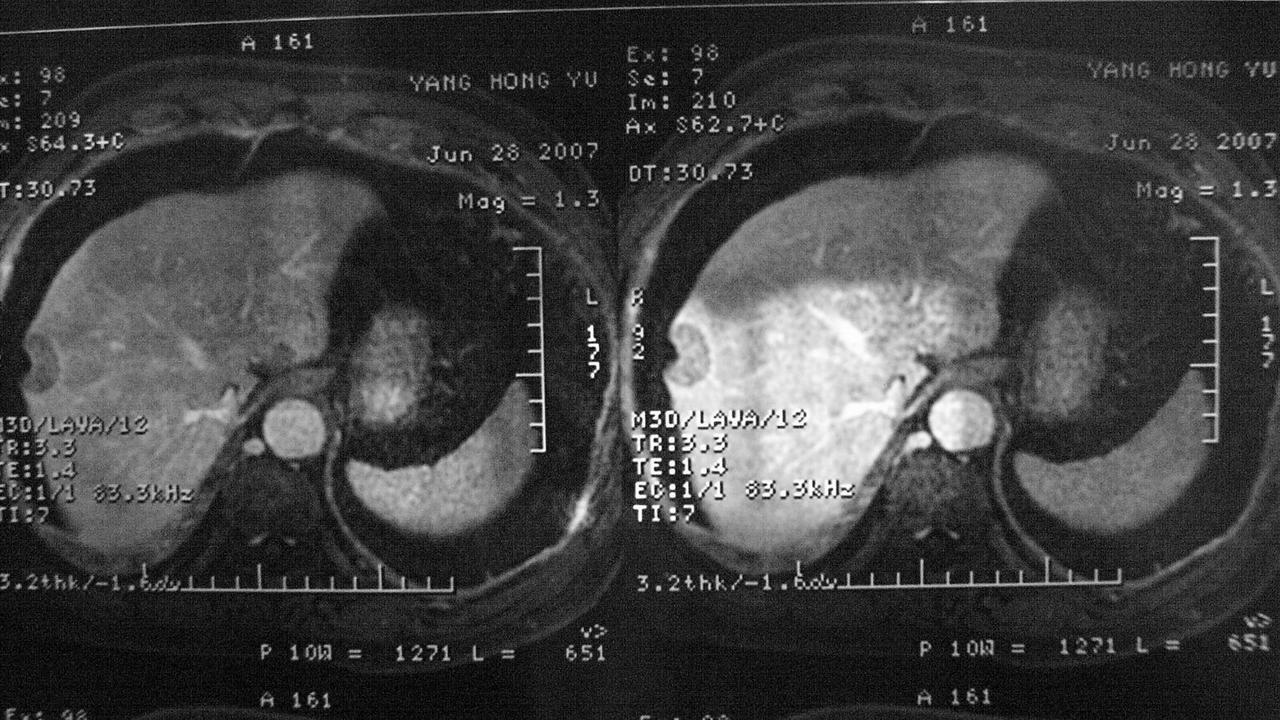

>>>>>>>>提问请帮我看看这张X光片,病情在哪里?如何治疗?要知道,救人一命能造7个宝塔,所以,千万不能乱回答,一定要回答清楚!我需要知道病因、治疗方法……越详细越好,但并不是要冗余内容,而且一定要有效方法,要知道,人命关天!千万不能乱说啊!

第三层:从X光片看,在肝脏偏下部位有一肿瘤生成.

第四层:应该及时的做肿瘤的切片化验,确定肿瘤的性质.

第五层:如果确定是良性肿瘤,可以采取中医药治疗方法.

第六层:如果确定是恶性肿瘤,应该尽快手术治疗,术后放化疗一段时间为好.

第七层:保持乐观心情,不管是病人还是家属.心情对疾病的治疗是很关键的.